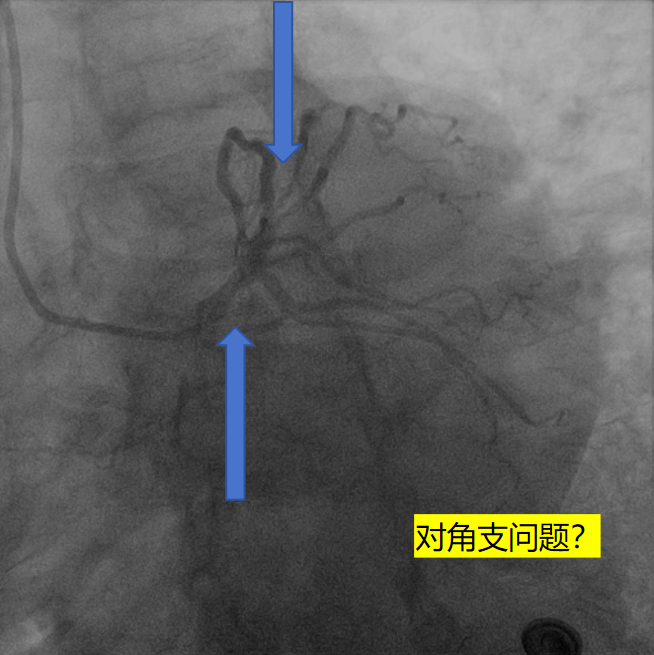

1、有症状,心电图有变化,造影提示临界病变;

2、提示罪犯病变可能是左主干or对角支。腔内影像学+功能学评估罪犯血管?

1,过导丝,通过病变,行IVUS

2,由远至近IVUS评估,不同切面对应不同面积,提示左主干面积4~5mm²,属于重度狭窄,需要介入治疗。

3,担心guiding深插对开口2次损伤,放窦外导丝进一步保护,根据ivus指导,植入4.0x18mm 支架。

4,不同体位确定开口位置,释放支架。

5,植入后,复查ivus,评估支架植入效果。

6,IVUS 评估后,最小面积未达到8mm²最小官腔面积。需进一步后处理。

介入经过——最后影像

7,给与4.0x15mm非顺应性球囊进行高压后扩张,压力维持在16~20atm。最后检查血管影像。